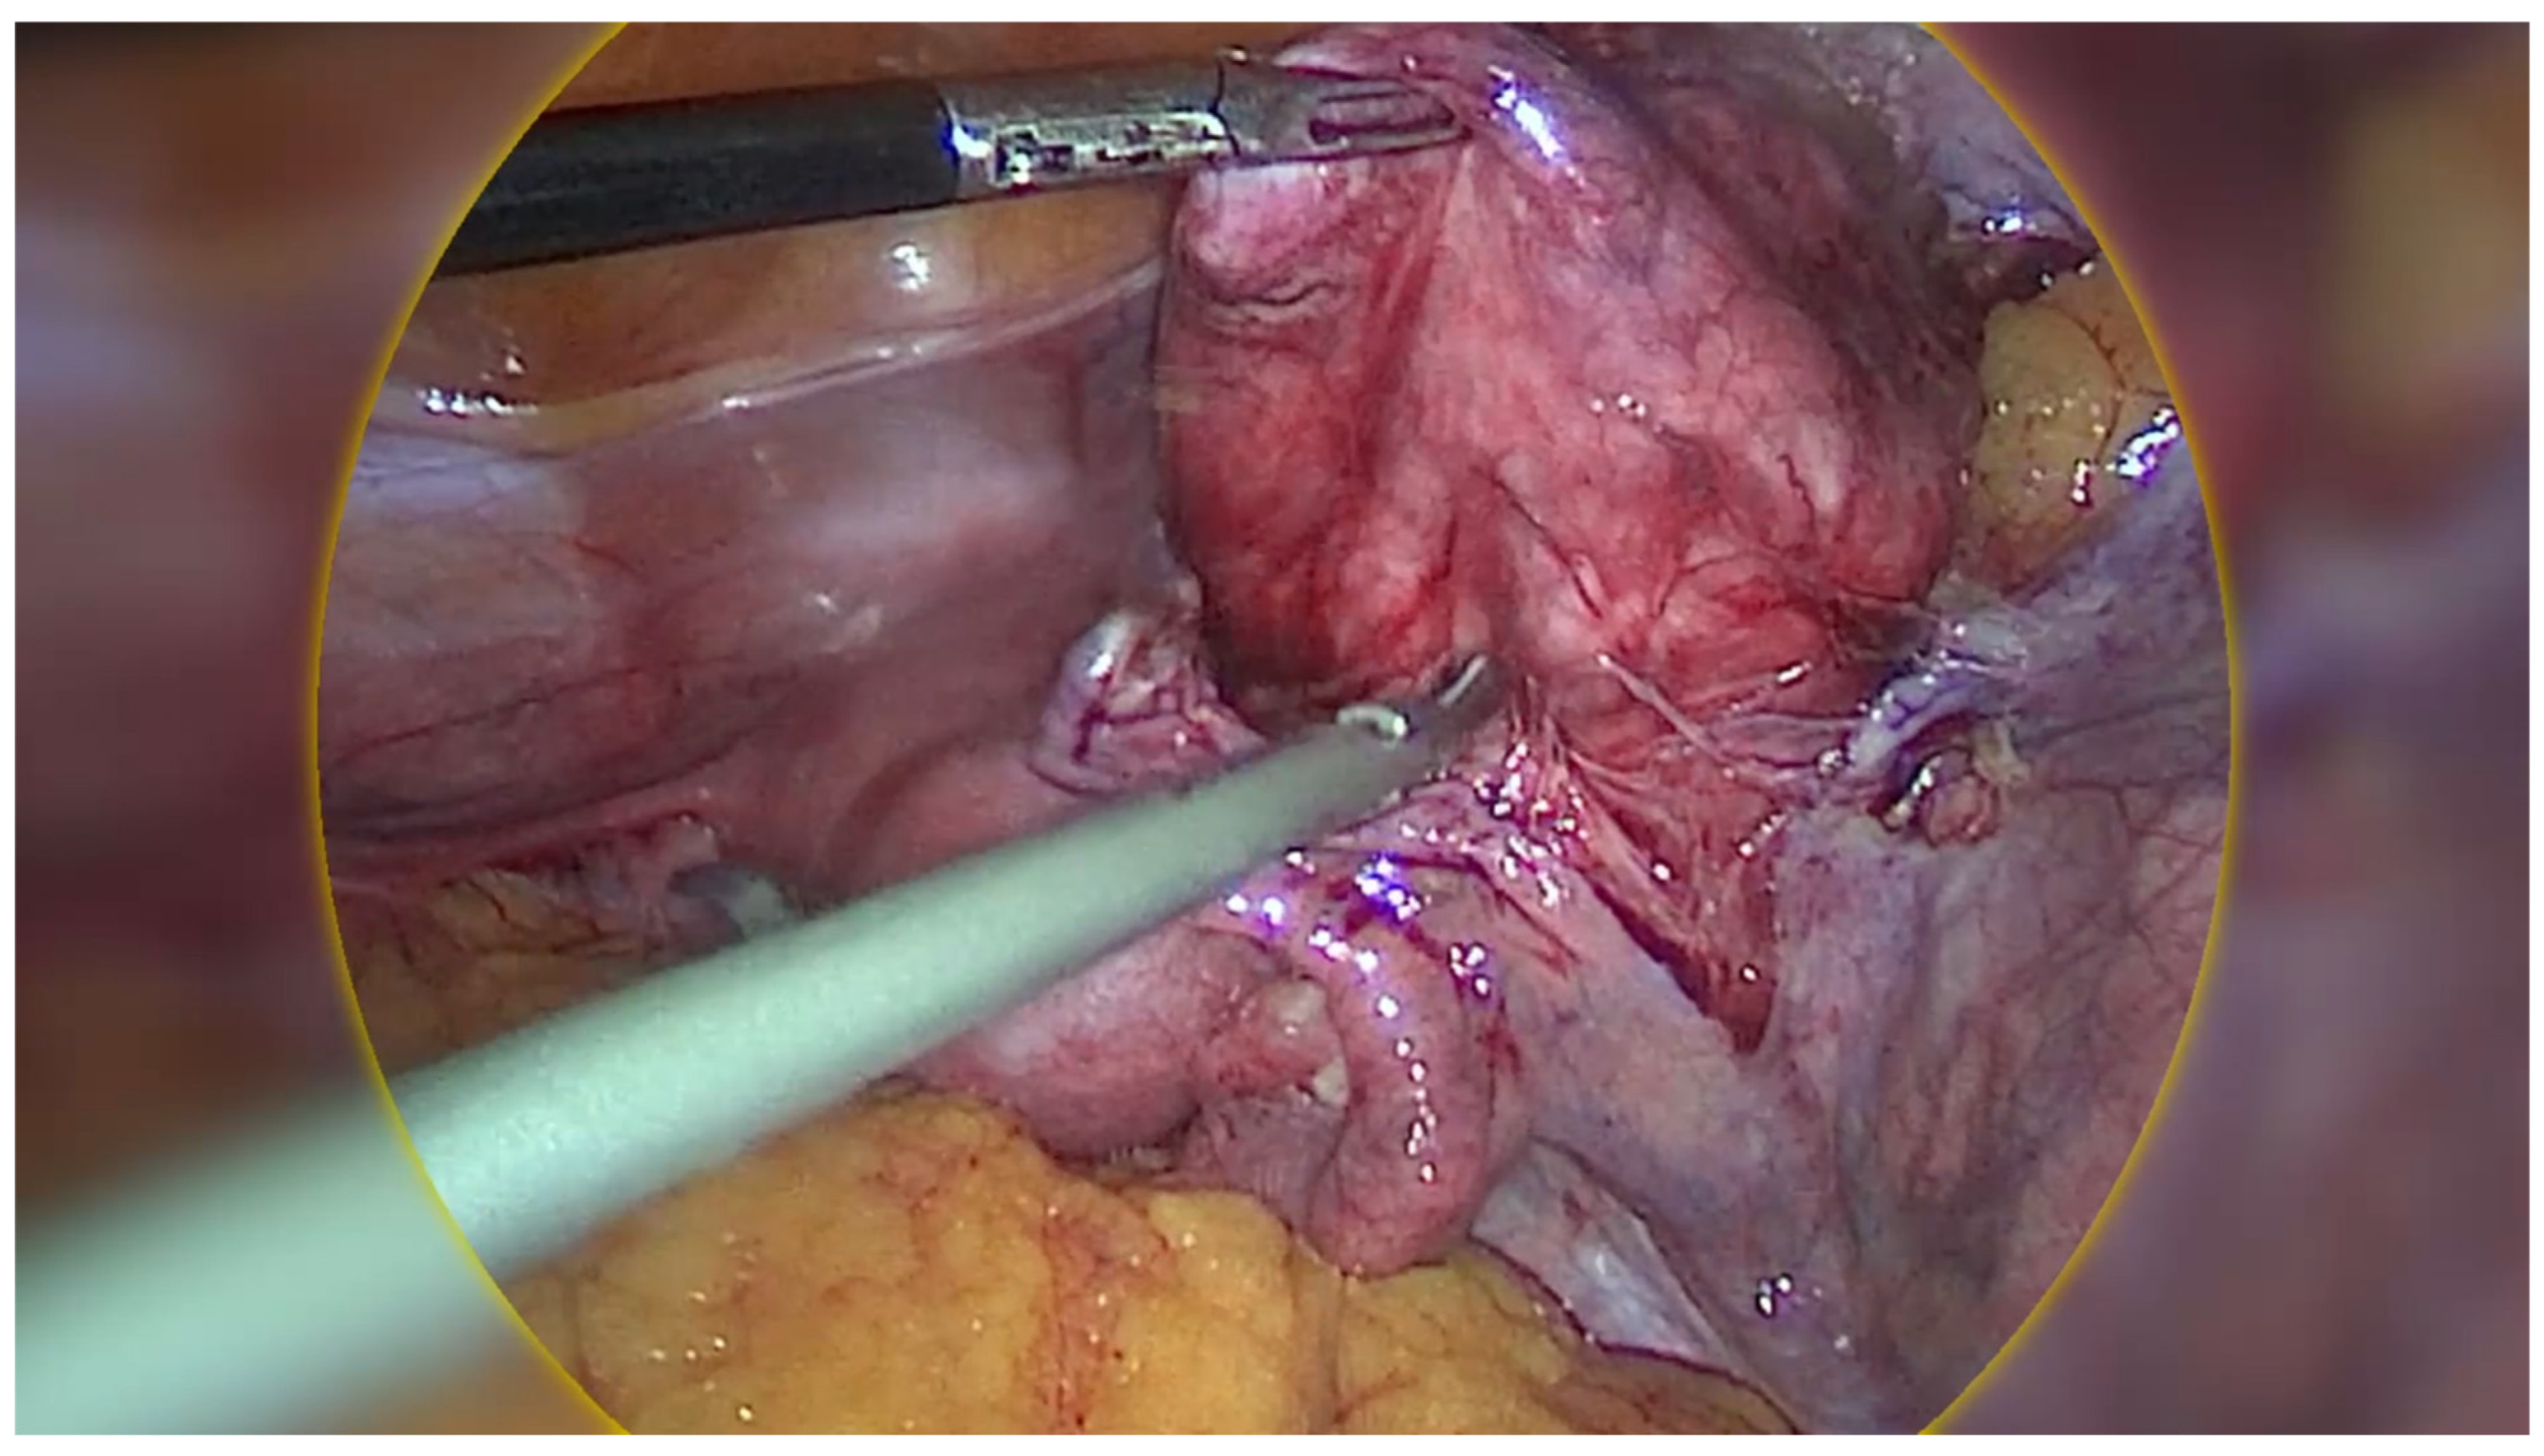

Regarding the ovarian tumour, the patient underwent a diagnostic laparoscopy using a 4-port laparoscopic technique with an ipsilateral configuration, during which we were met with an intra-operative surprise. A retroperitoneal pelvic mass of unknown origin was found and further explored. The mass measured around 8 x 8 cm and was found to be attached to the uterus laterally, anteriorly extending up to the paravesical space, laterally to the external iliac vessels, and posteriorly in the pararectal space (Figure 2). Initially, the mass was thought to be a fibroid, however on palpation the consistency of the mass was different to that of a usual fibroid and was soft, almost jelly-like. The gross features also resembled cotyledons of the placenta (Figure 3). Due to the unique pattern of growth and inconclusive appearance of the retroperitoneal mass, we consulted with a gynaecology oncologist intra-operatively via telehealth and proceeded with their recommendation to perform an excisional biopsy.

Figure 3. Intra-operative image of cotyledonoid dissecting leiomyoma (CDL) which grossly resembles cotyledons of the placenta.